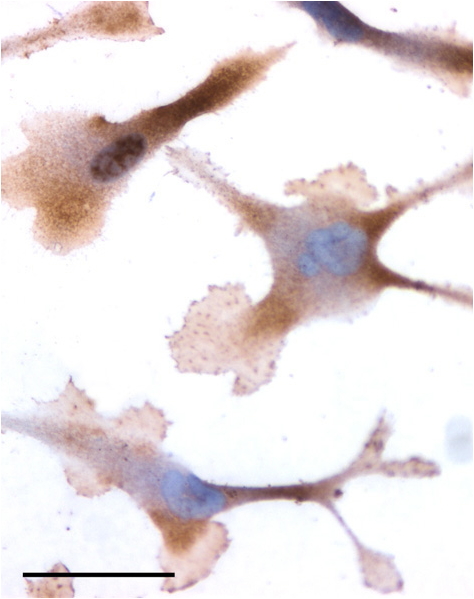

IHC Results In paraffin embedded Human Prostate Cancer shows staining of the stromal component of smooth muscle. Recommended concentration: 2-4µg/ml. | |